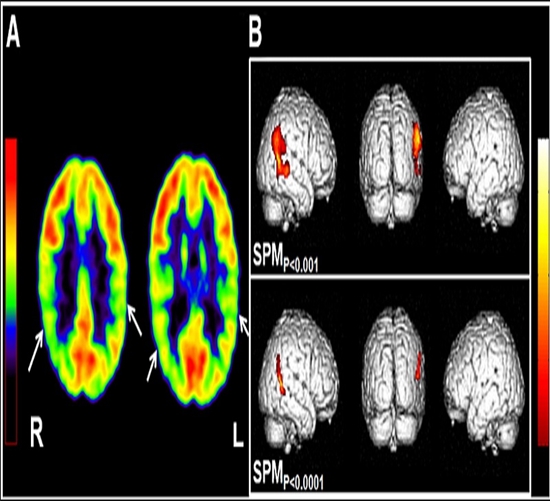

بررسی همبستگی نتایج آنالیز کمّی و کیفی در تصویربرداری PET/CT بیماران صرع لوب تمپورال در ایران

با توجه به حساسیت 50 درصدی تصاویر PET برای تشخیص صرع لوب تمپورال، نتایج بدست آمده از آنالیزهای کمی در تایید و کمک به تشخیص ناحیه درگیری موثر است. با توجه به اینکه تشخیص ناحیه درگیری، ممکن است در نهایت برای تشخیص کانون صرع و جراحی آن ناحیه منجر خواهد شود، حصول اطمینان از صحت تشخیص دیداری، بسیار حیاتی خواهد بود. در حال حاضر یکی از بهترین روش های کمک کننده به تشخیص دیداری صرع لوب تمپورال، آنالیز عددی نقاط مختلف مغز است.با در اختیار داشتن آنالیز کمّی، پزشکان می توانند نتایج را ارزیابی و به نتیجه دقیق تری در مورد کانون درگیری دست یابند. هدف از این تحقیق بررسی و مقایسه نتایج حاصل از آنالیز کمّی تصاویر پت مغزی بدست آمده با استفاده از نرم افزارهای مخصوص آنالیز مغز، با گزارش های دایداری پت توسط پزشکان می باشد.

نتایج حاصل از این بررسی ها گامی موثر در جهت اعتبار بخشیدن به گزارش های دیداری پزشکان می باشد؛ در صورت همخوانی نتایج بدست آمده از آنالیز کمّی با نتایج دیداری ارائه شده توسط پزشک، قطعیت تشخیص بالا می رود، در صورت عدم همخوانی نتایج، با بررسی عوامل ایجاد اختلاف و مرتفع ساختن آنها، مجددا به صحت تشخیص و بررسی کمک خواهد شد.